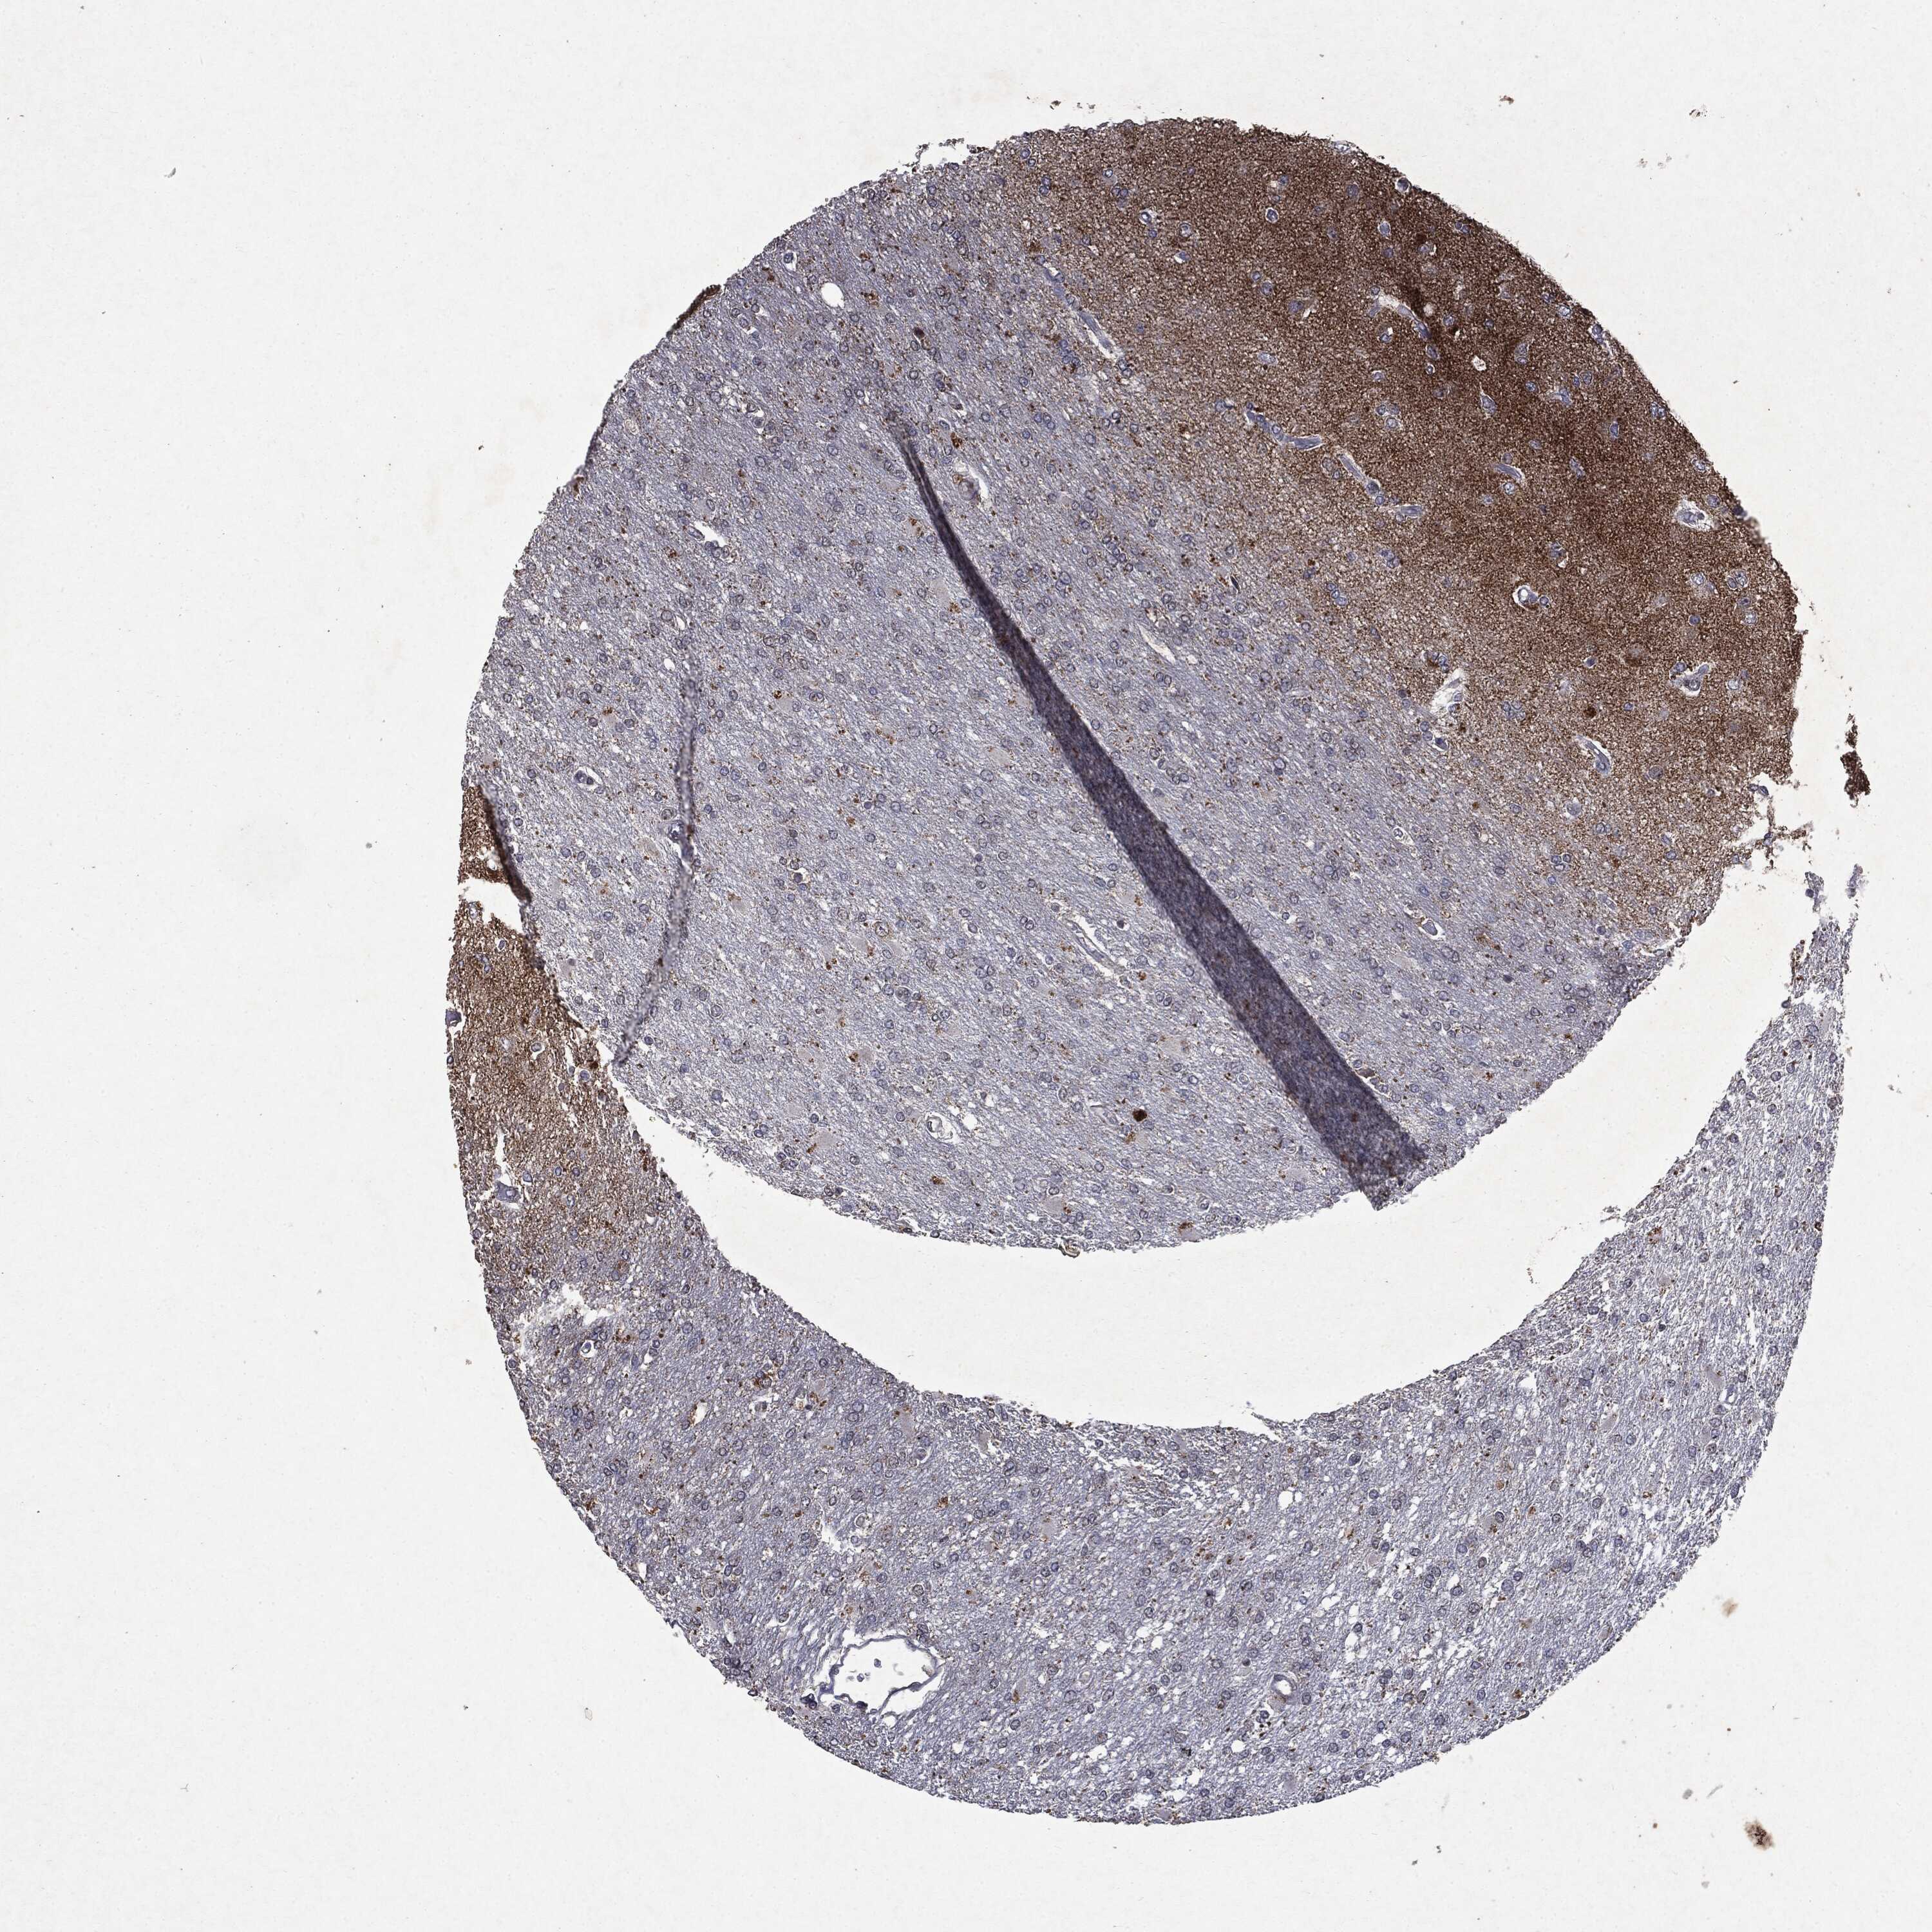

GLIOMA - Protein expressioni

A mouse-over function shows sample information and annotation data. Click on an image to view it in a full screen mode. Samples can be filtered based on level of antibody staining by selecting one or several of the following categories: high, medium, low and not detected. The assay and annotation is described here.

Note that samples used for immunohistochemistry by the Human Protein Atlas do not correspond to samples in the TCGA dataset.

Antibody stainingi

Antibody staining in the annotated cell types in the current human tissue is reported as not detected, low, medium, or high, based on conventional immunohistochemistry profiling in selected tissues. This score is based on the combination of the staining intensity and fraction of stained cells.

Each image is clickable and will lead to virtual microscopy that enables deeper exploration of all samples and also displays staining intensity scores, fraction scores and subcellular localization as well as patient and tissue information for each sample.

Antibody HPA031335

Antibody CAB004076

Antibody CAB080153

Antibody CAB080157

Glioma, malignant, Low grade

Glioma, malignant, High grade

Glioma, malignant, NOS